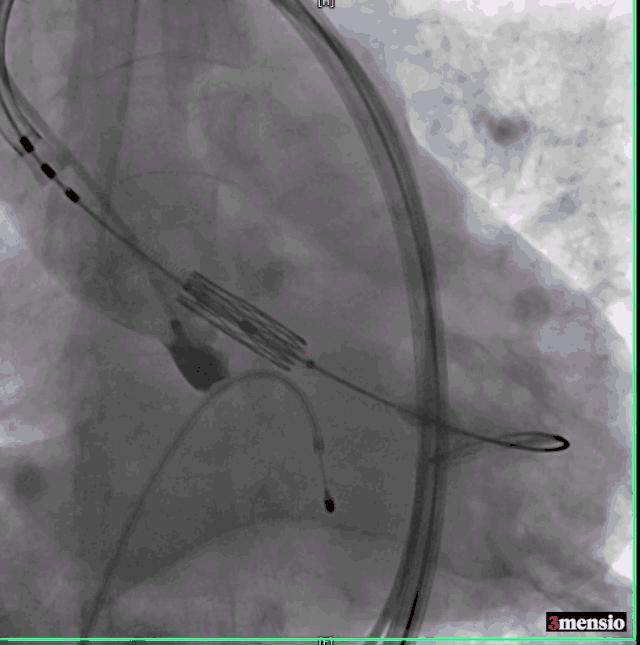

危险在此时发生了,球囊扩张后,患者出现血压下降,造影发现钙化的瓣膜扩开后出现大量反流,手术团队当即决定马上植入已经预装好的23号瓣膜,且因为预扩张球囊的反馈情况,把原有定额17ml减少2ml至15ml,成功跨瓣后精确定位并在临时起搏器180次/分起搏控制血压下于高位释放,过程顺利。

瓣膜定位

瓣膜释放